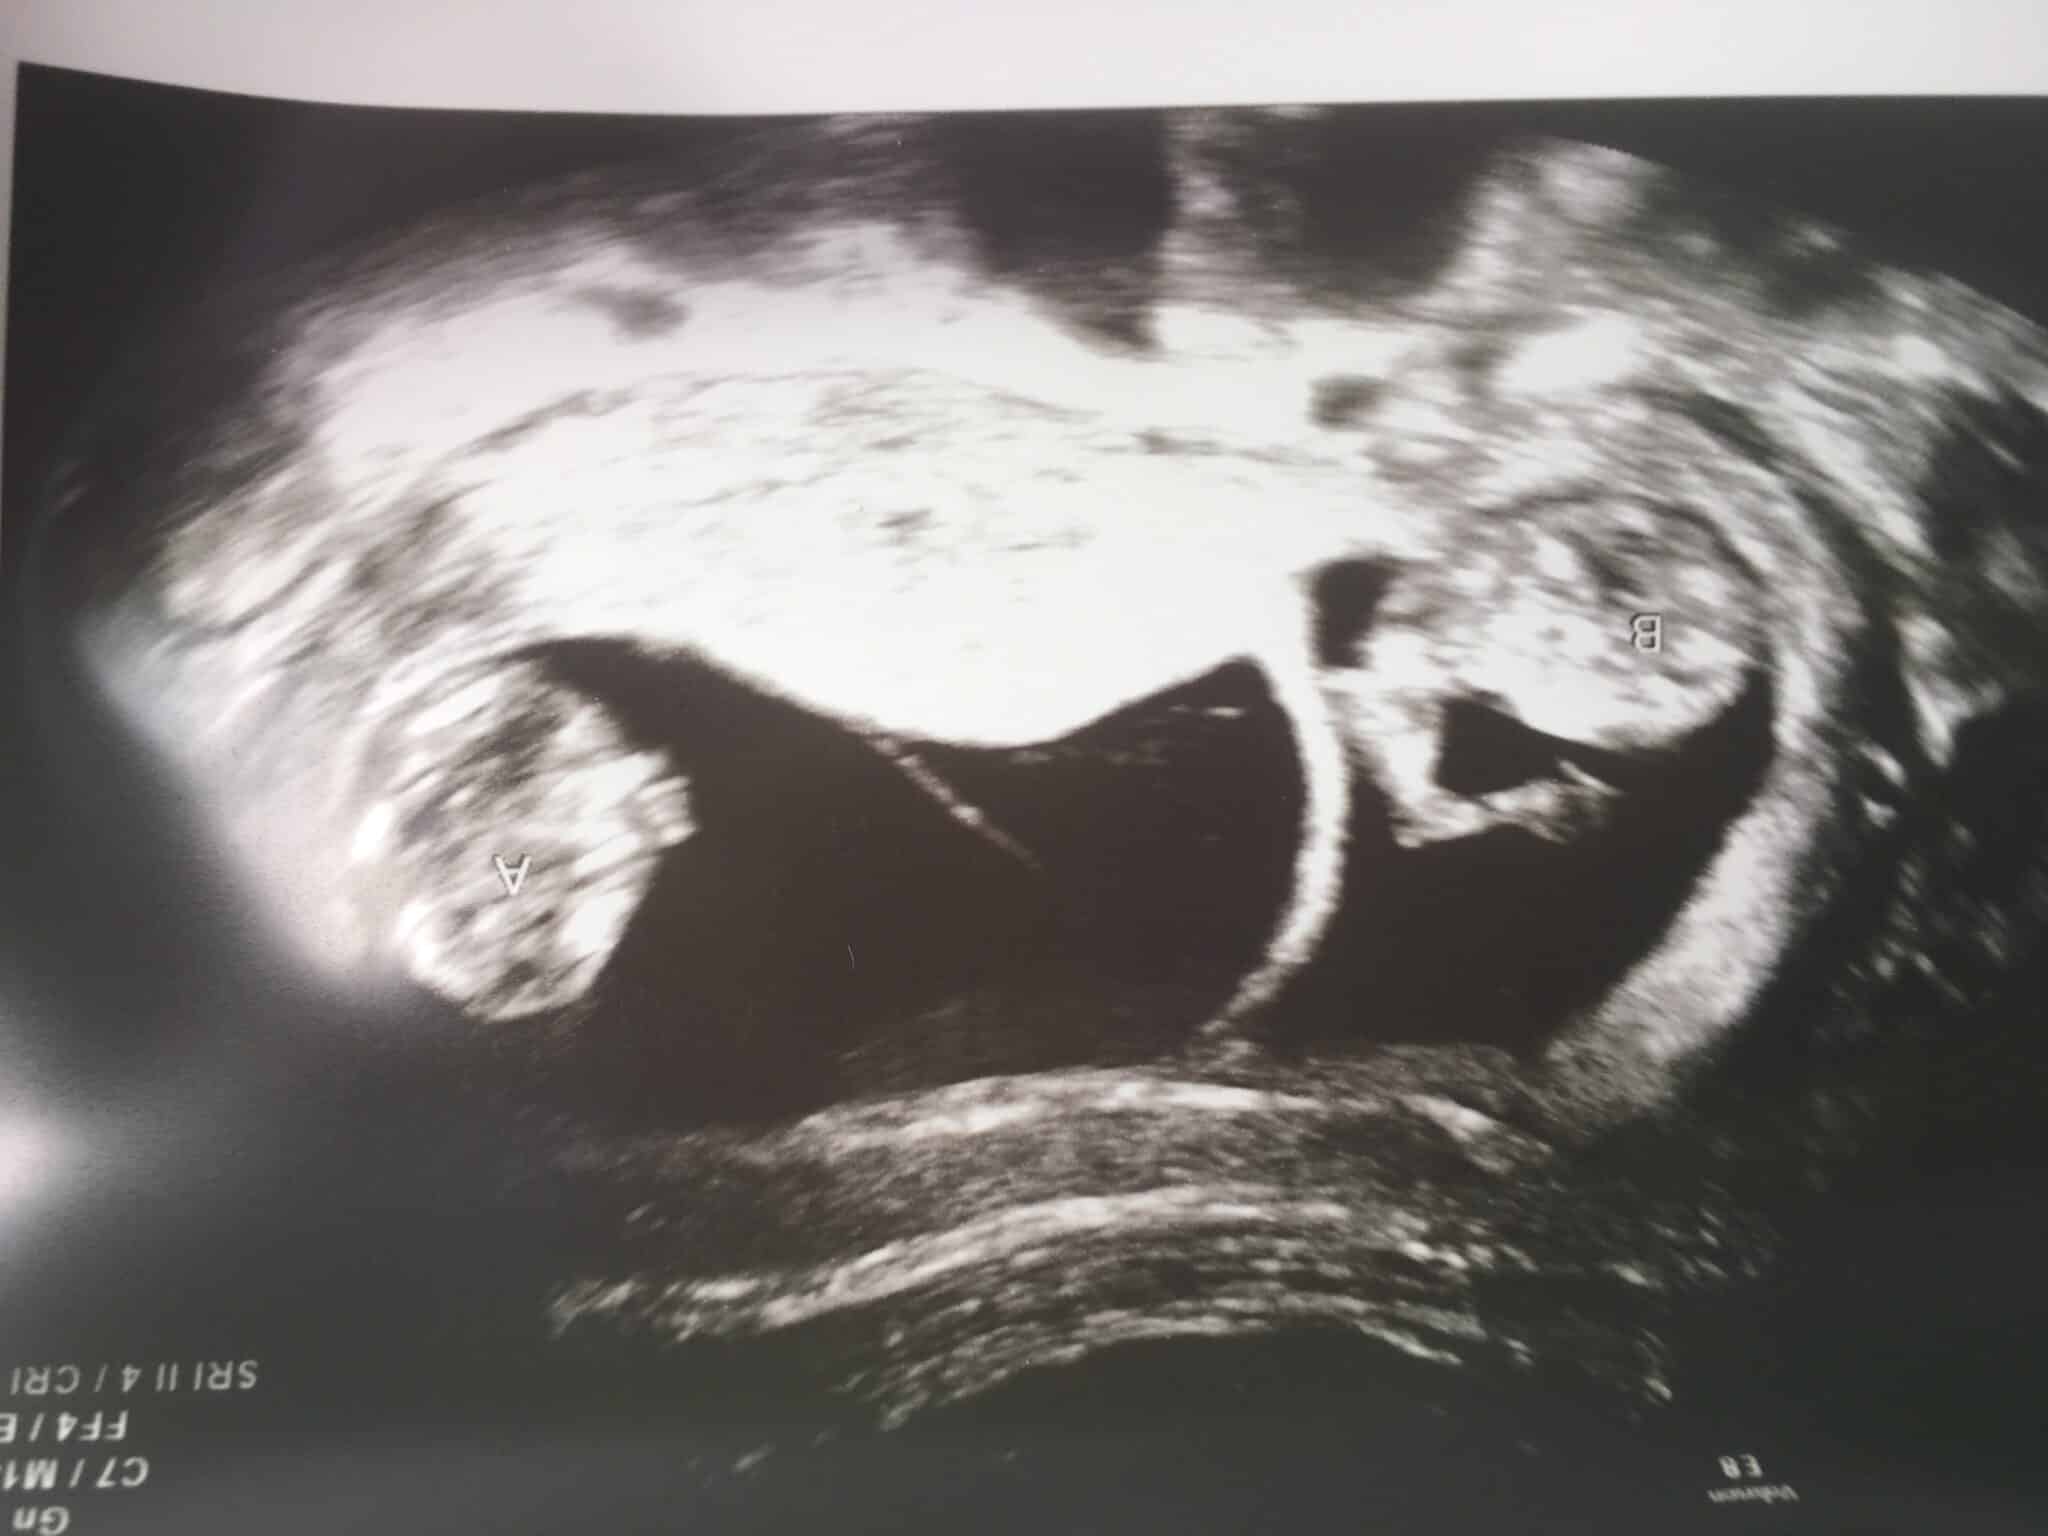

Ultrasound Photos at 11 Weeks Pregnant With Twins